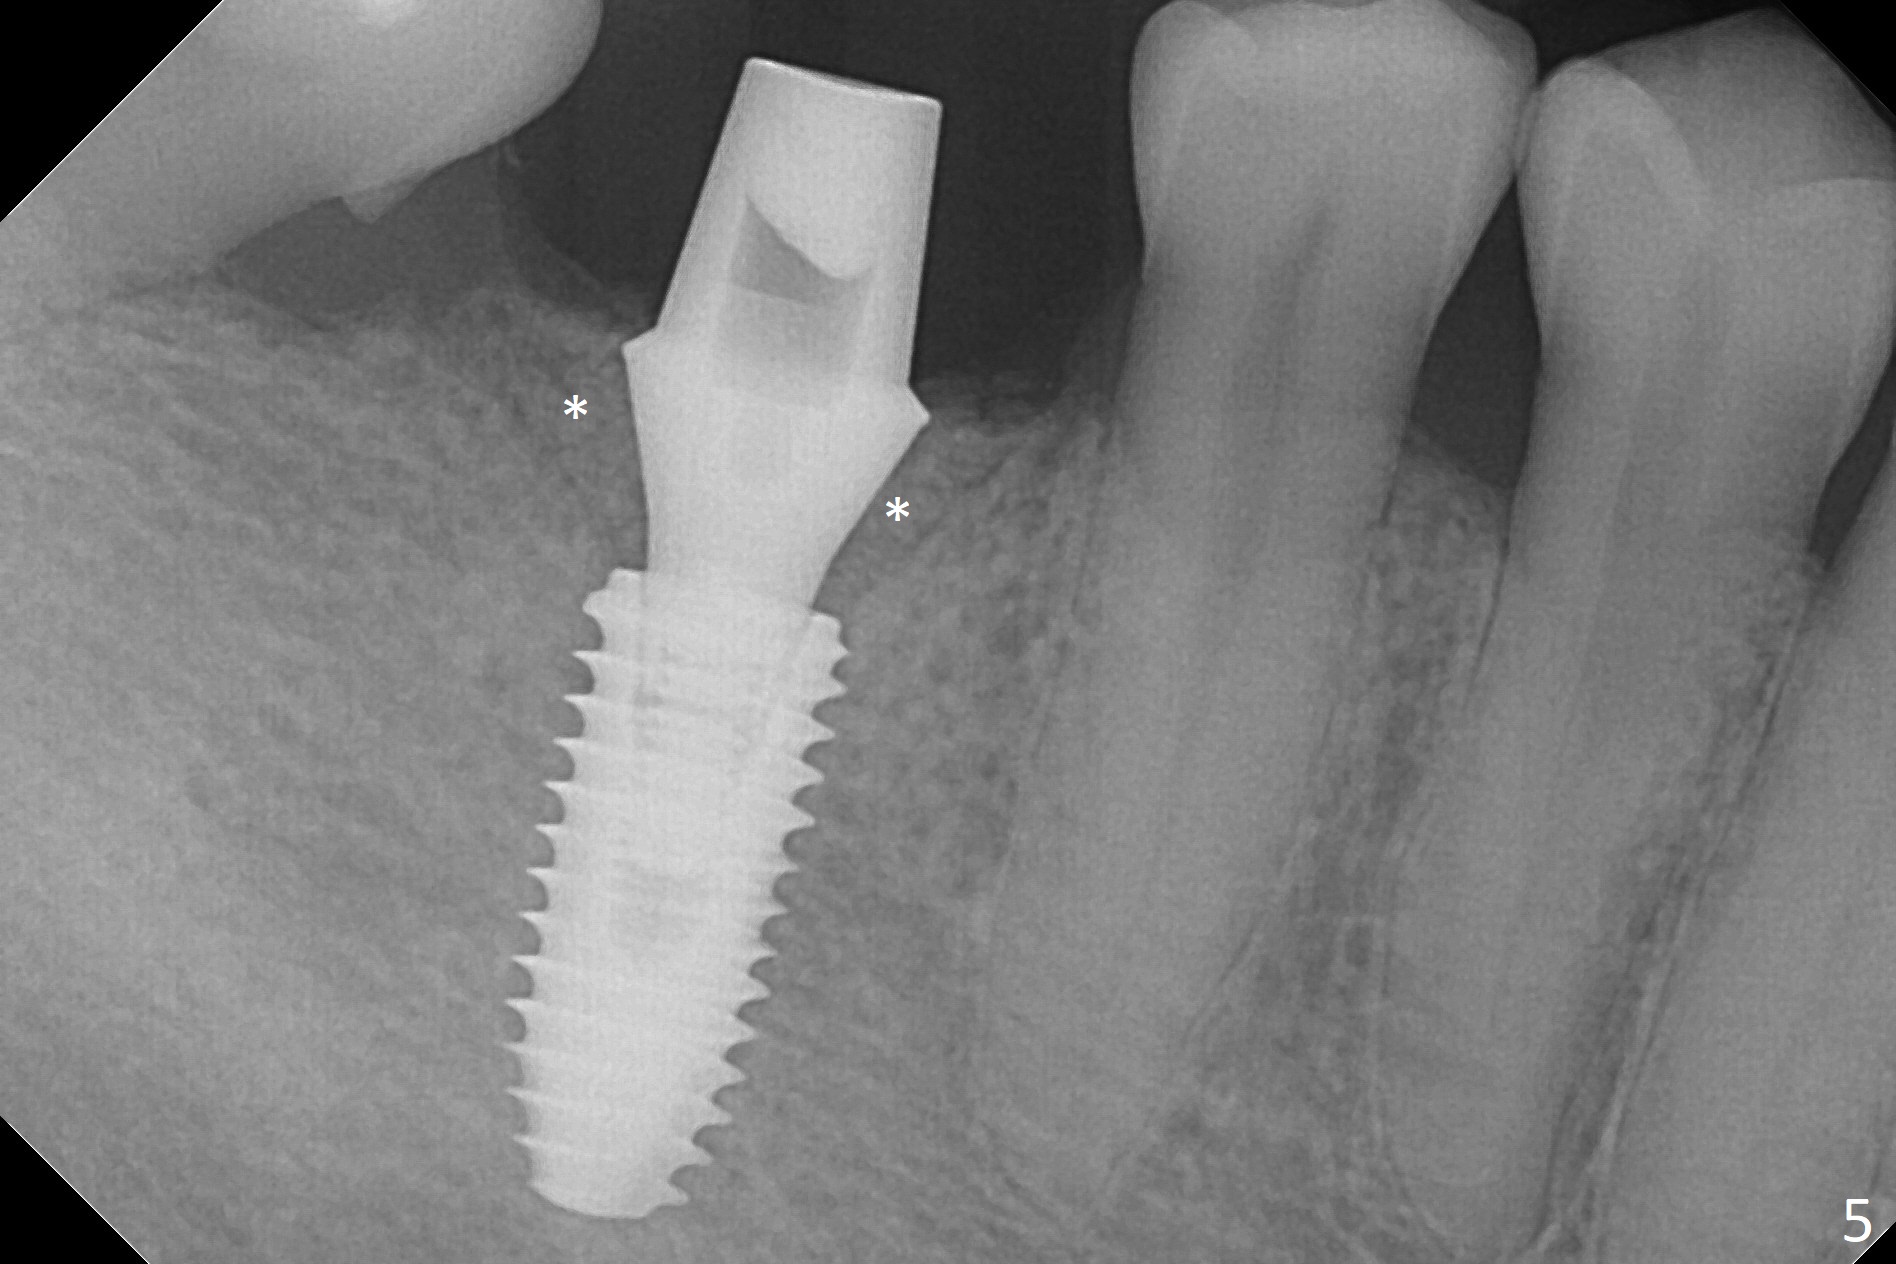

When the residual roots of the tooth #30 (Fig.1) are removed, the buccal crest is found ~ 2 mm apical to the lingual one (Fig.2 <); while the initial depth of osteotomy is 11.5 mm (yellow lines), the parallel pin is 10 mm long.  To place a 5x11.5 mm implant at the level of the buccal crest (Fig.4 (>45 Ncm)), subsequent osteotomy depth is 13 mm using the lingual crest as a landmark (Fig.3 (4 mm drill in place)).  After insertion of a 5.7x5.5(3) mm abutment, Vanilla Graft is placed (Fig.5 * with 2 mm buccal gap).  The abutment with a provisional is loose 4 months postop (Fig.6).   The permanent restoration is cemented 6 months postop.  The abutment screw is loose and fractured 8 and 11 months post cementation, respectively (Fig.7).  The fractured screw seems to be loose within the implant well and is easily re-winded out using Screw Removal Kit (sr-kit.html).  When the crown/abutment at #30 is loose 2nd time 1 year 7 months post cementation (Fig.8 taken post retightening), the screw at #19 fractures.  The tooth #2 needs a crown.  The patient cannot use the anterior teeth, since the teeth #8 and 9 have root fracture.  Can extraction and bone graft increase bone height?  The screw re-fractures 9 months later (Fig.9).  The dislodged crown is sectioned; the abutment is reseated completely (Fig.10) for a new crown. The tooth #2 needs RCT, B-U and crown, while the tooth #1 extraction (Fig.11).